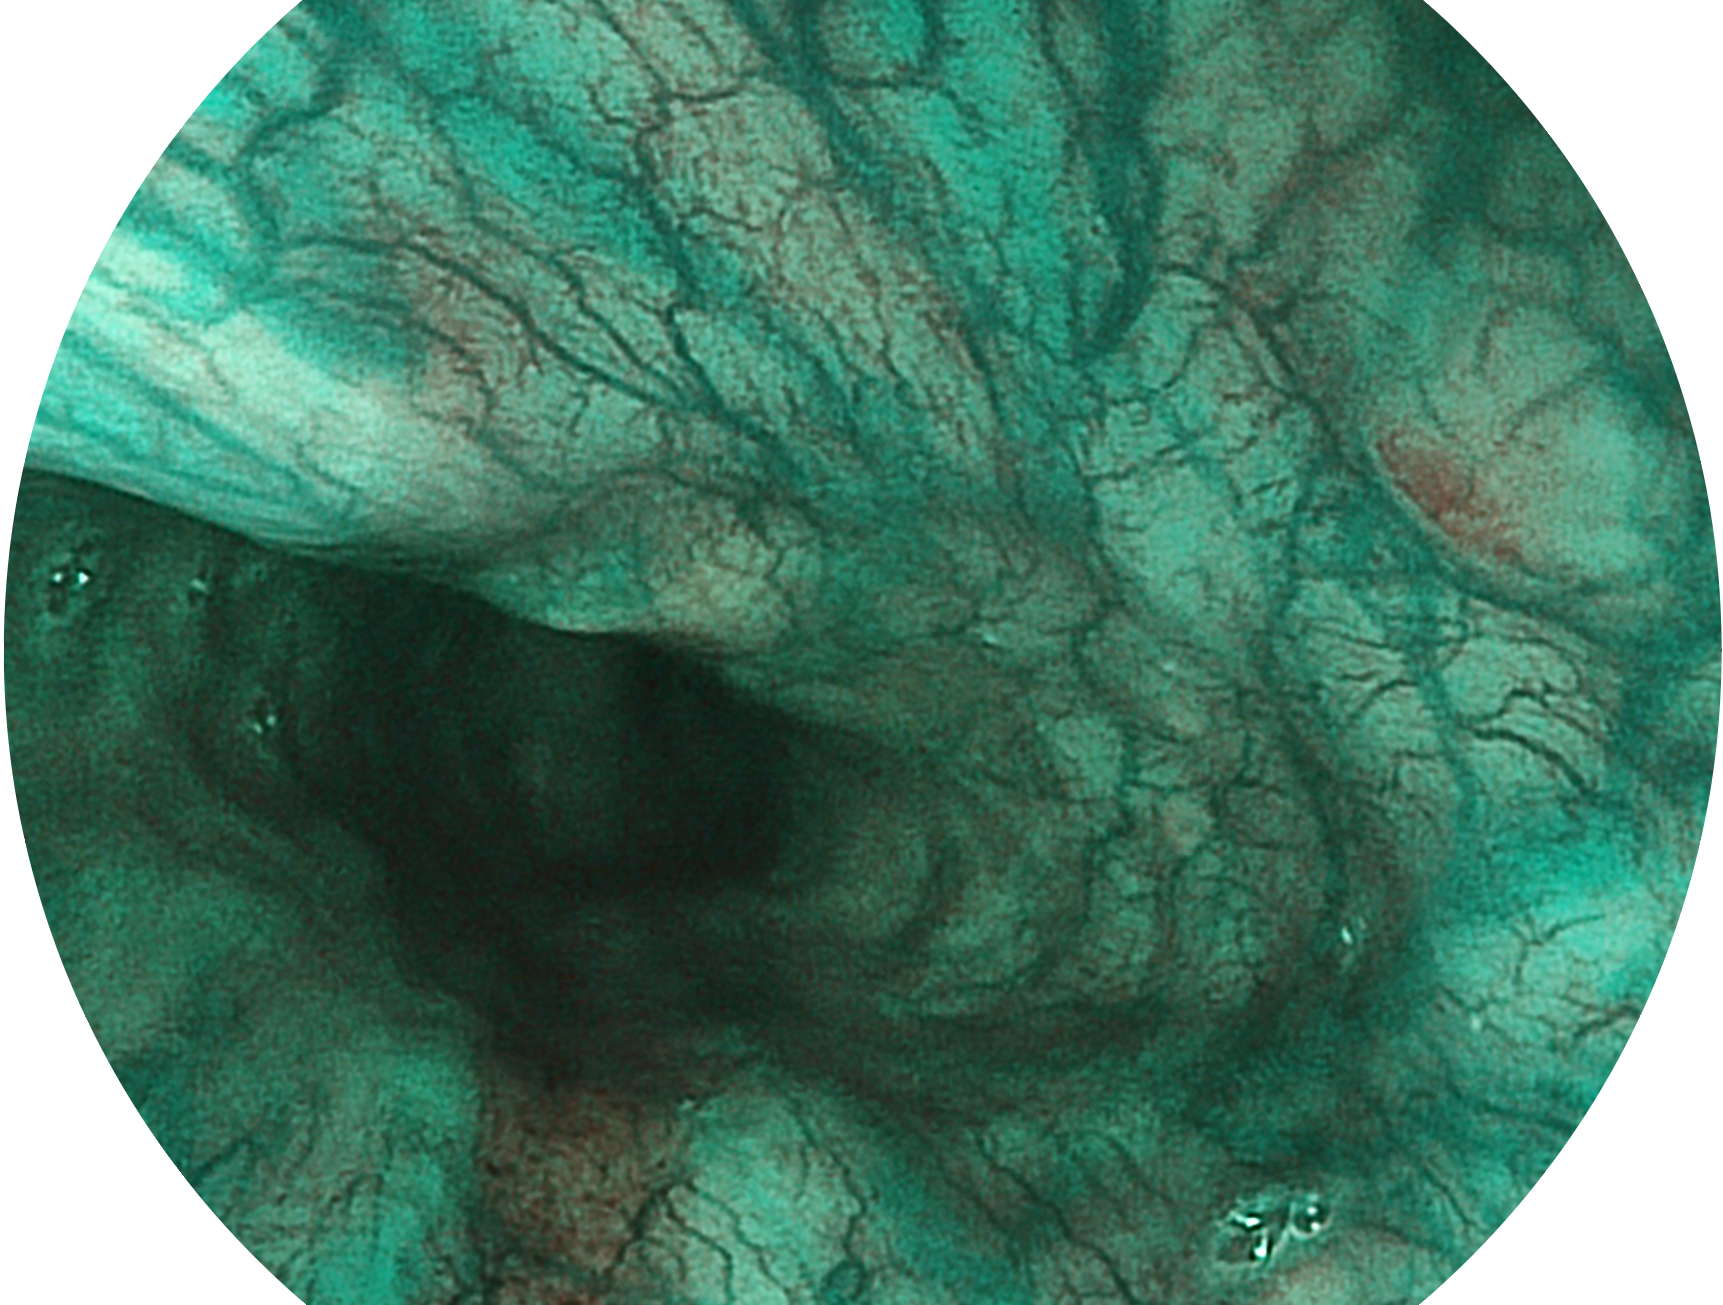

百老汇电子游戏官网新开发的内镜染色技术,主要是基于多波长LED 光源的开发,VLS-55Q 四波长LED 光源是由四个不同颜色的LED光按照相应照明模式所规定的特定发光比例进行合束后形成,合束后形成的照明光的光谱由红光、绿光、蓝光及蓝紫光这四个不同的波段范围构成。具有更高光谱自由度,通过光谱比例的控制,实现了聚谱成像技术,英文全称为“Spectral Focused Imaging, SFI”,缩写为“SFI”和光电复合染色成像技术,英文全称为“Versatile Intelligent Staining Technology, VIST”,缩写为“VIST”。